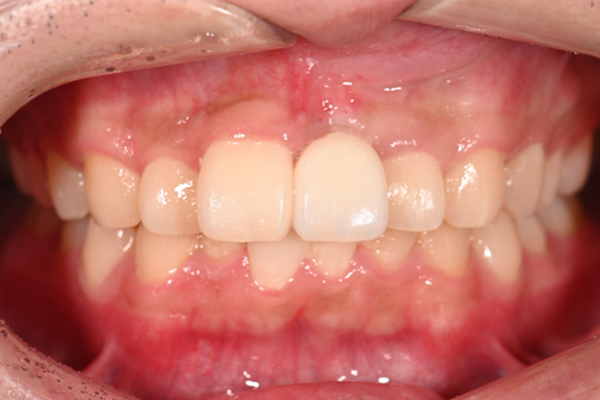

| 主訴 | 歯がグラグラして噛めない |

|---|---|

| 治療内容 | 上顎、下顎に対するインプラント治療 |

| 治療期間 | 1日 |

| 治療費 | 409万2千円 |

| 治療 リスク | 最終的な歯が入るまでは仮歯になります。 |